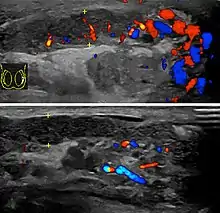

Rhabdomyosarcoma (a) Longituidinal section (composite image) of high resolution ultrasound of a 14-year-old boy shows a well defined hypoechoic extratesticular mass is found in the left scrotum, hydrocele is also present. (b) Color Doppler ultrasound shows that the mass is hypervascular.

Rhabdomyosarcoma is the most common tumor of the lower genitourinary tract in children in the first two decades, it may develop anywhere in the body, and 4% occur in the paratesticular region which carries a better outcome than lesions elsewhere in the genitourinary tract. Clinically, the patient usually presents with non-specific complaints of a unilateral, painless intrascrotal swelling not associated with fever.

Transillumination test is positive when a hydrocele is present, often resulting in a misdiagnosis of epididymitis, which is more commonly associated with hydrocele. The ultrasound findings of paratesticular rhabdomyosarcoma are variable. It usually presents as an echo-poor mass [Fig. 11a] with or without hydrocele. With color Doppler sonography these tumors are generally hypervascular.